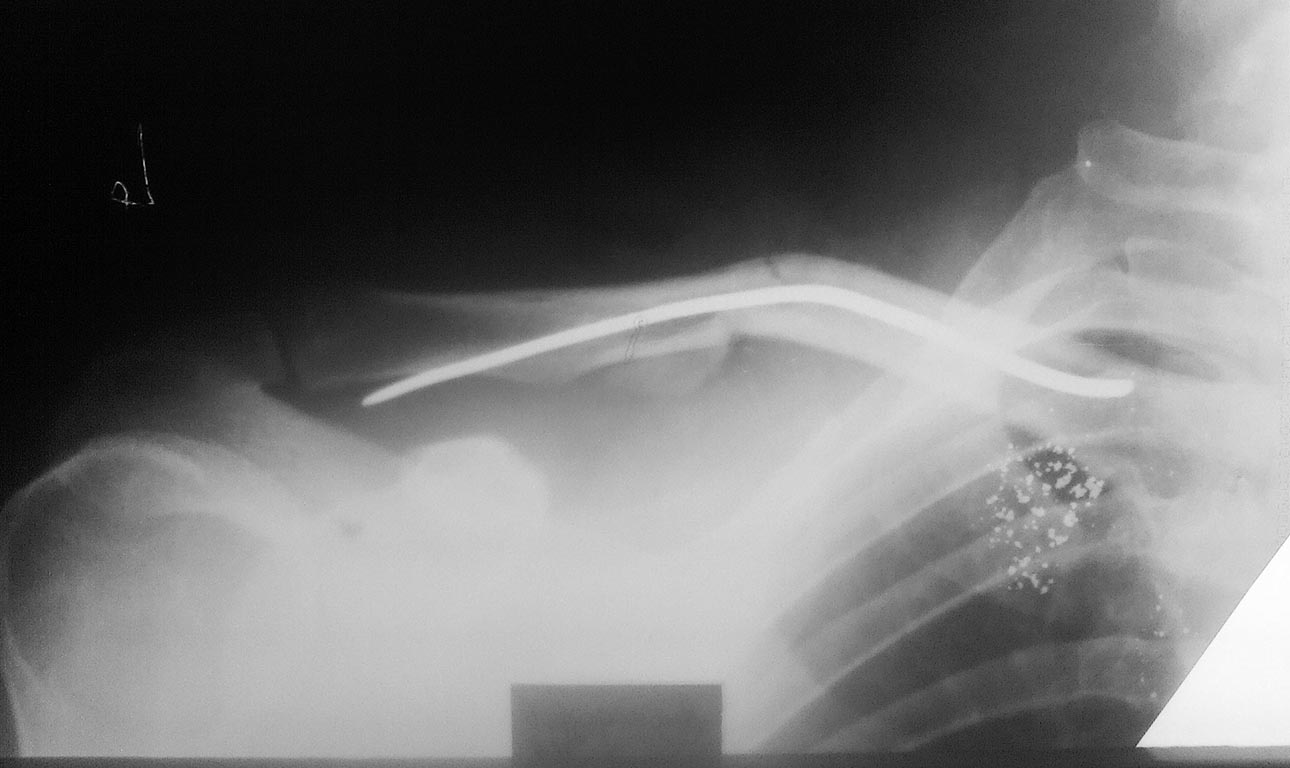

Мужчина, 35 лет, 23.11.15 получил закрытый оскольчатый перелом левой ключицы в результате падения на руку с высоты роста.26.11.15 выполнена операция: Открытая репозиция, интрамедуллярный остеосинтез штифтом Богданова, промежуточные осколки фиксированы на место лавсановыми нитями.

Остеосинтез выполнил по классической методике: через доступ длинной 5 см экономно скелетировал отломки, рассверлил сверлом 3.2 мм каналы в дистальном и проксимальном отломках, подобрал соответствующего диаметра стержень Богданова, который антеградно ввбил в репонированные отломки,промежуточные осколки фиксировал лигатурами к месту перелома.

Смущает одно, что изначально стержень не изгибал под S-образную кривизну ключицы, а на R-графии после остеосинтеза стержень деформировался под изгиб ключицы. Изначально планировал стержень расположить "широкой" частью фронтально, но не вышло.

Остеосинтез не стабильный. Гвоздь Богданова уже согнут, в дальнейшем может сломаться на уровне перелома, и получим несращение и проблему с удалением. . Учитывая что вы делали доступ 5см, скелетировали отломки, связывали осколки нитями, т.е достигли репозиции отломков. Оптимально считаю учитывая, что прошло мало времени после операции, удалить гвоздь, выполнить стабильный реостеосинтез пластиной и спокойно вести конечность на косыночной повязке.

"... Гвоздь Богданова уже согнут..." - гвоздь деформировался под изгиб ключицы при вбивании, а не при неправильном ведении больного в послеоперационном периоде.

"не изгибал под S-образную кривизну ключицы"...зато природа сделала своё.Изгиб стал такой же,как и на здаровой ключице!Хотя,по снимкам, выглядит как "без пяти" сроссшийся перелом,не?...по снимкам перелом правой ключицы.